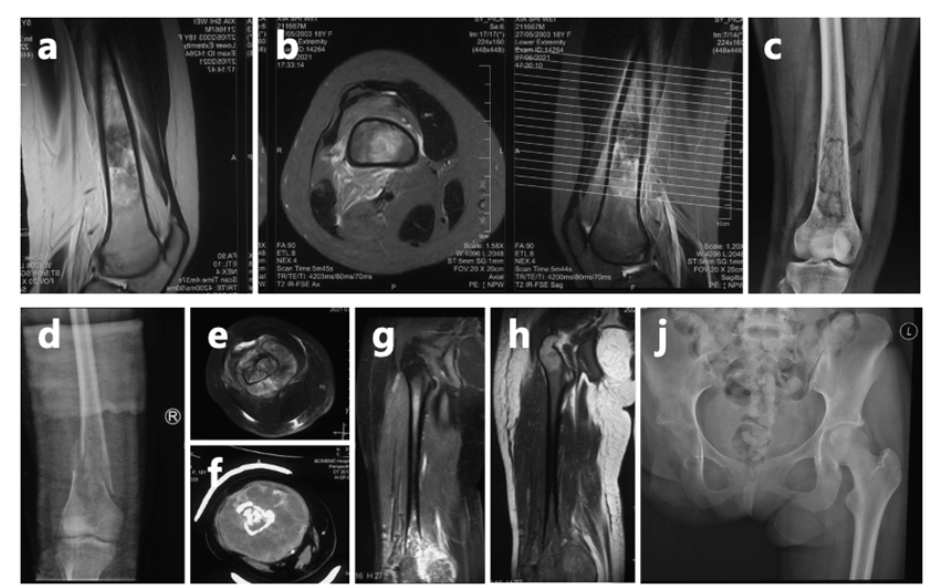

她说:“习惯一个人了。”在她的社交账号上,年龄那一栏,她郑重地填上了“100岁”。一个23岁的骨癌晚期女孩,最大的愿望,是能活到100岁。 这不是玩笑,这是她对生命最深切、最直白的渴望。 上海医生全力救治 巩固疗效、延长无病生存期 抗癌少女夏夏的故事 在网络传播后 她的乐观与坚强不仅鼓舞了 无数与恶性骨肿瘤斗争的患者 也深深感动了医护人员 上海市第一人民医院骨肿瘤科曾讲述过夏夏的经历:她确诊骨肉瘤后经历了6次手术和无数次挑战,自2023年8月接诊以来,又完成了10次化疗和2次手术。医护人员回忆,第一次见到夏夏,她戴着假肢,拄着拐杖,拉着一个与她身高差不多的行李箱,独自走进医院。这一幕让人既心疼又敬佩。 市一骨肿瘤科介绍,对于夏夏来说,此前的截肢是一个相对可靠的选择。由于肿瘤已推挤下肢的血管和神经,并累及髋关节,截肢手术能够降低肿瘤复发的几率。然而,截肢会导致术后肢体功能的永久性丧失,对患者心理和生活质量可能造成一定影响。尽管困难重重,她始终以微笑和坚韧面对一切。

夏夏前期接受了术前化疗、截肢手术及术后化疗,使用的是一线化疗方案。然而,结疗不到一年,肺部出现转移病灶,这种情况是恶性肿瘤的普遍特性,骨肉瘤患者中并不少见,尤其是结疗后2年内,是转移和复发的高发期。 为帮助她巩固疗效并延长无病生存期,2024年2月,夏夏经过手术切除后未再进行化疗。术后5个月,左肺再次发现新发转移病灶。2024年11月,夏夏接受胸腔镜下右肺下叶切除术。2025年1月复查:右肺术后改变好转。